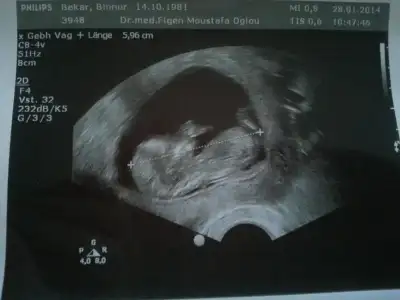

Bebegim 12+6 gunluk burada. Doktor cinsiyeti icin erken dedi. Elimizdeki tek resim bu.

Yorumlarinizi esirgemeyin.

kiz ihtimali yuksek